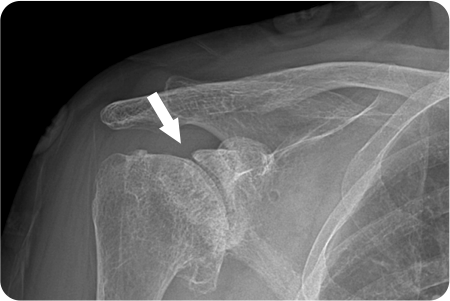

어깨 관절염

인공관절치환술

관절염으로 닳아버린 손상된 연골과 뼈를

정밀하게 절제합니다. 환자의 상태에 따라

전치환술/반치환술 중 선택하여 시행

합니다.